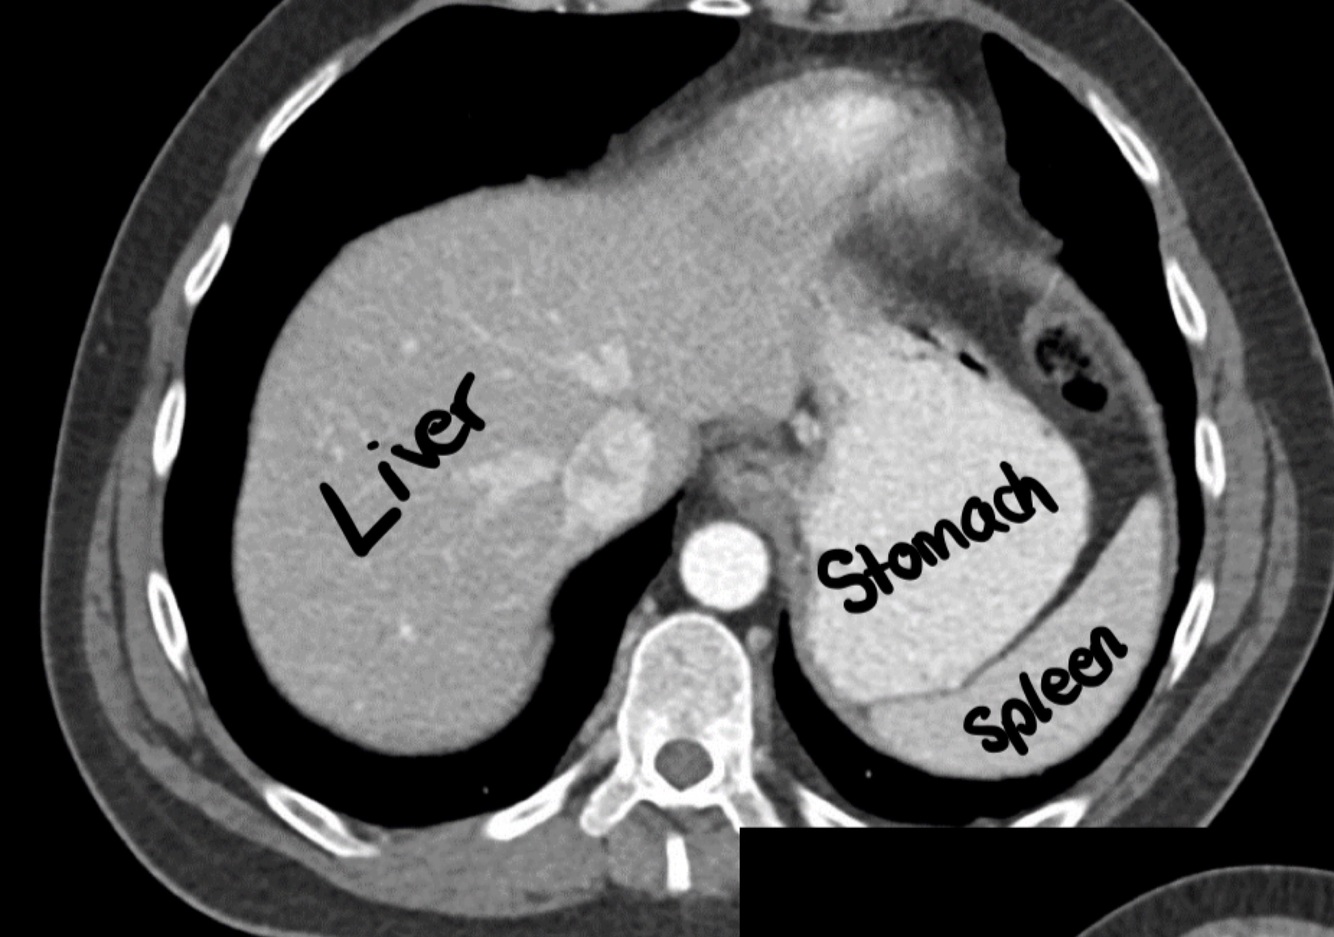

Abdomen topography

CT (bones are hyperintense)

How well did you know this?

In the supramesocolic region, we find…

Liver, stomach and spleen